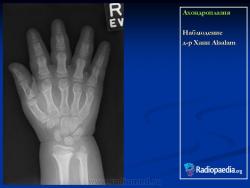

Ахондроплазия

Дело 1

Случай 3